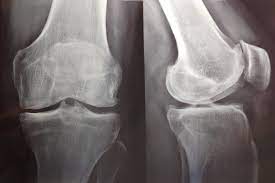

Artrosis de rodilla: eficacia y seguridad de la viscosuplementación

Existe evidencia concluyente de que la viscosuplementación conduce a una pequeña reducción en el dolor de la osteoartritis de rodilla en comparación con el placebo, que resulta menor a la diferencia mínima clínicamente importante. También hay evidencia concluyente de que la intervención se asocia con un riesgo aumentado de eventos adversos graves, por lo que se considera que estos hallazgos no respaldan su uso generalizado en el tratamiento de la artrosis de rodilla. British Medical Journal, 6 de julio de 2022.